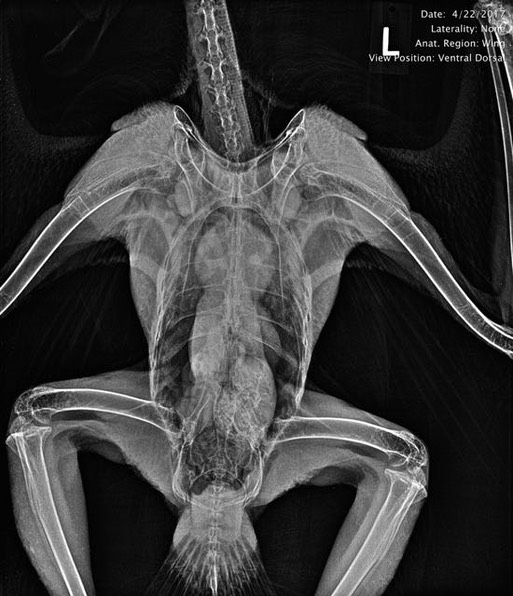

Joe and Cordi Atkinson found an injured Swainson’s Hawk at the base of a power pole on their ranch near Vale, OR. It was one of a pair who have nested on the ranch for a number of years. Tara was again called on to help transport the bird to Pendleton.

An exam revealed the hawk was in excellent physical condition, especially amazing considering she had just completed her spring migration from Argentina to eastern Oregon. We also found burns on both feet and a small wound and broken primary feather on her right wingtip, indicating she had been electrocuted.

A radiograph confirmed slight swelling in her right wingtip.